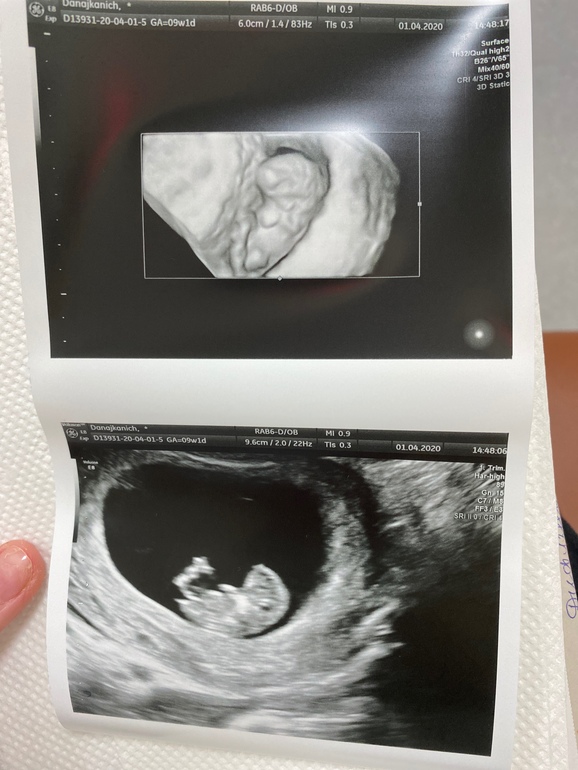

А вот и наше первое 3д фото и обычное:

Плодное яйцо 57*41*20

КТР 26мм, что отвечает 9 неделям и 2 дням, прям все тютелька в тютельку:))

Сердцебиение 178уд/мин

ЖМ 5мм

Хорион на задней стенке, толщина 9,0мм

Длина шм 30мм